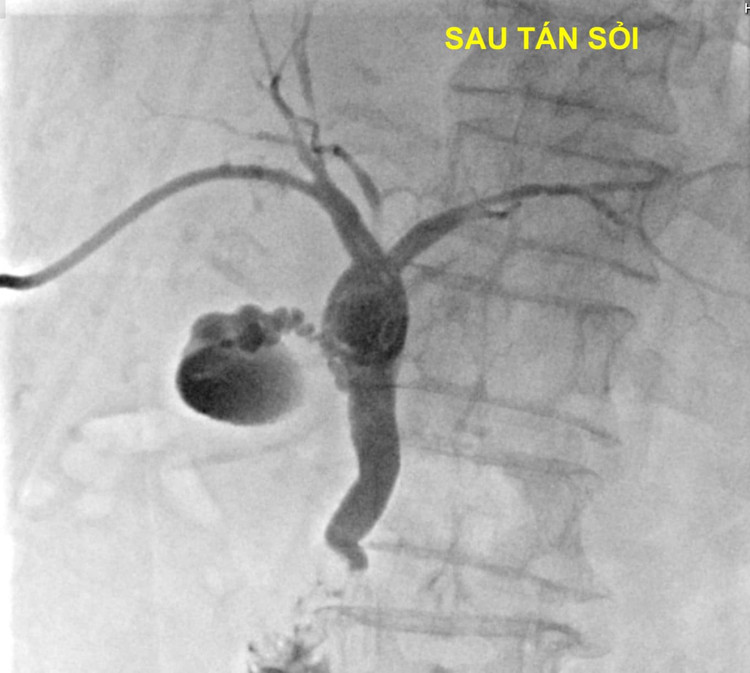

![]() |

| Hình ảnh sỏi mật trước và sau khi tán |